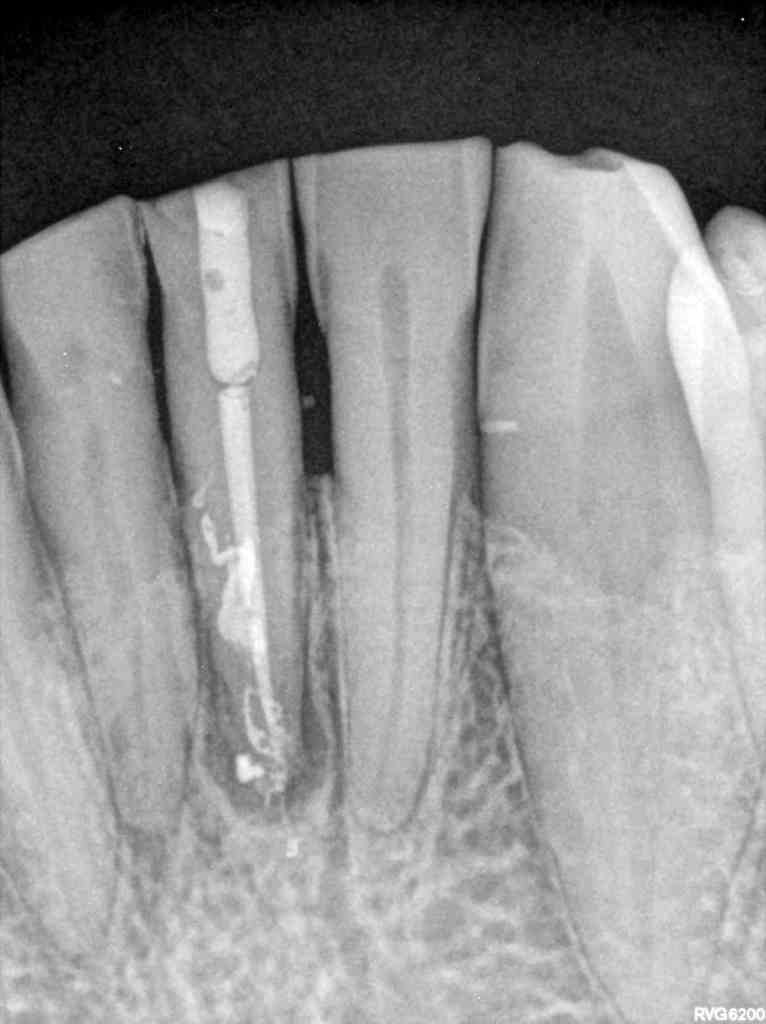

El paciente acude a la consulta en 2022 con sintomatología compatible con necrosis pulpar en el diente 3.1. Tras la confirmación diagnóstica, se realiza el tratamiento de conductos. Un año después, el diente 4.1 presenta un cuadro clínico similar, asociado a la sobrecarga funcional derivada del bruxismo. Se diagnostica necrosis pulpar y se procede igualmente a realizar tratamiento endodóntico. En 2025, el paciente acude con la presencia de una fístula vestibular a nivel del 4.1. Tras la evaluación clínica y radiográfica, se concluye la existencia de una fractura radicular vertical, lo que compromete el pronóstico del diente (Figuras 1-6).